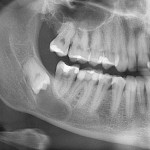

Клиническая ситуация выясняется в ходе предоперационного обследования, наиболее важным из которых является компьютерная томография: